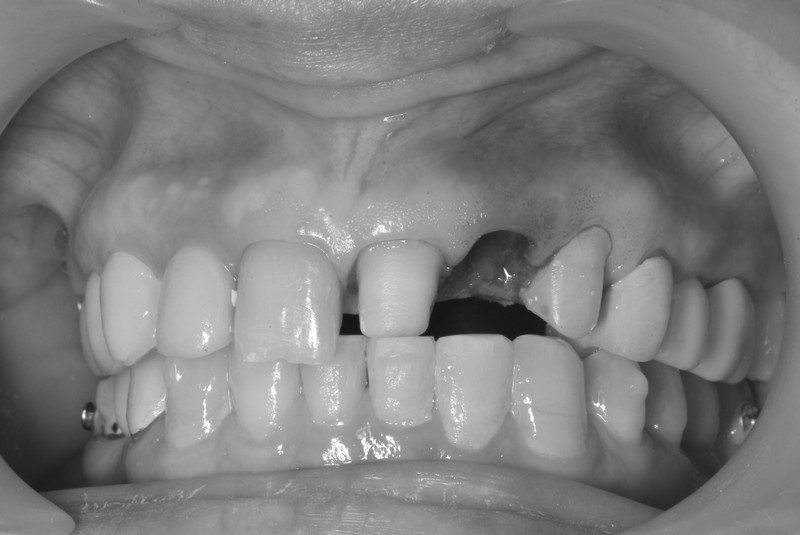

前牙美學植牙